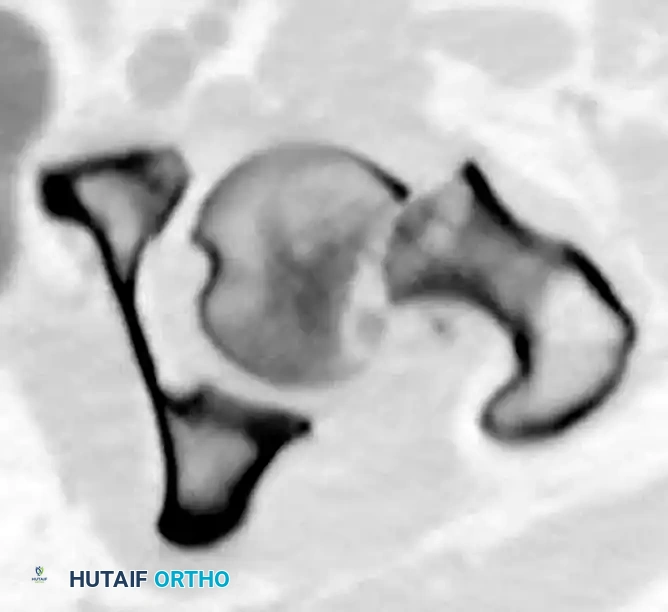

Evaluating the Reduction

Intraoperative fluoroscopy is used to critically evaluate the reduction before any hardware is placed.

The Garden Alignment Index

This index evaluates the alignment of the compressive trabeculae of the femoral head relative to the medial cortex of the femoral shaft.

* Ideal Alignment: On the AP view, the angle should measure exactly 160 degrees.

* Valgus Malalignment: An angle greater than 180 degrees indicates excessive valgus, which can lead to superior joint penetration by hardware as the fracture settles.

* Varus Malalignment: An angle less than 160 degrees (e.g., 150 degrees) indicates varus. This is the most dangerous malreduction, as it converts compressive forces into shear forces, almost guaranteeing fixation failure.

On the lateral image, the angulation should be approximately 180 degrees. Deviation of more than 20 degrees indicates excessive anteversion or retroversion and is unacceptable.

Trabecular Alignment and Lowell's S-Curves

Beyond the Garden Index, the trabecular alignment pattern must be scrutinized. The medial compressive trabeculae should flow seamlessly from the femoral head into the calcar femorale.

Lowell et al. described the fluoroscopic appearance of an anatomically reduced femoral neck as forming "shallow S- or reverse S-shaped curves" along the superior and inferior cortices. These curves are highly sensitive indicators of rotational alignment and may be more practically useful intraoperatively than measuring specific angles.